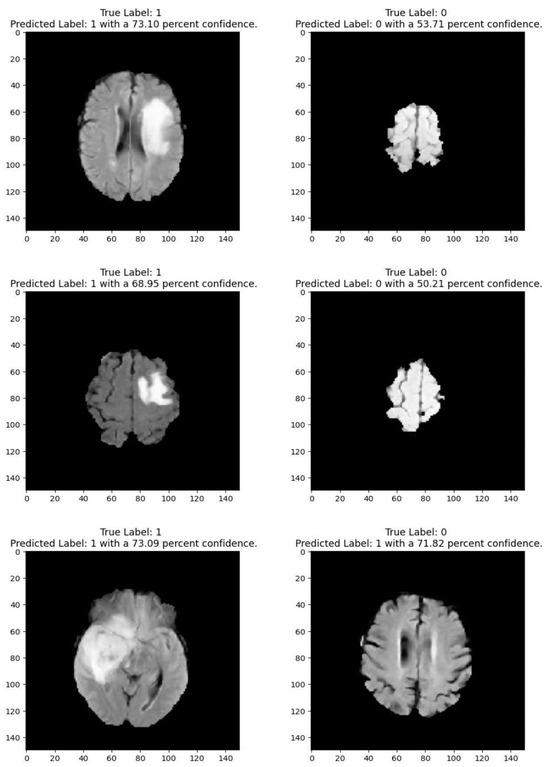

Figure 2 shows that images depicting no tumor typically reveal a serene landscape of brain tissue, characterized by uniform intensity and well-defined anatomical structures. MRI images exhibiting tumors offer a stark contrast. Within these scans, areas of heightened intensity or irregular masses emerge, signaling the presence of pathological growths. These tumors may manifest as distinct lesions, irregular masses, or regions of increased signal intensity, disrupting the otherwise orderly landscape of brain tissue. Notably, the presence of tumors often induces observable changes in adjacent structures, which may appear compressed, displaced, or distorted. By discerning these visual cues, healthcare professionals can effectively differentiate between images with no tumor and those with tumors, facilitating accurate diagnosis and informed treatment decisions for patients

Medical imaging encompasses a diverse array of variations, underscoring the significance of image detection in their interpretation. Our focus was on utilizing MRI scans for the detection of brain tumors. MRI serves as a common modality for both detecting and categorizing brain tumors. In our study, we opted to employ fine-tuned transfer learning models to aid in the identification of brain tumors due to their ability to make precise predictions regarding tumor cells. Figure 9, Figure 10, Figure 11 and Figure 12 display graphical representations of the base model combined with transfer learning operations, and Table 4 presents the corresponding findings. Figure 13, Figure 14, Figure 15 and Figure 16 illustrate the epoch-by-epoch progress of the proposed model, with Table 5 summarizing the associated results. We present a comparison in Table 6 of this study, contrasting the existing research with our proposed approach. Figure 17, Figure 18, Figure 19 and Figure 20 represent the prediction of the model in terms of tumor or non-tumor. The model, named Fine-Tuned Transfer Learning Xception, achieved the highest accuracy of 0.9611, as indicated in the table.